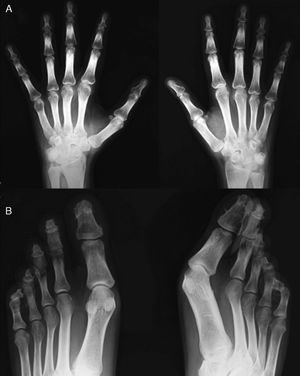

Clinical PresentationThe case is a 30-year-old male patient with a history of primary pulmonary hypertension without a shunt and followed by pediatric cardiology ever since. He had no other history of importance, including rheumatic disease or psoriasis. At age 29 he started presenting episodes of symmetric, additive polyarthritis which affected knees, ankles, shoulders, wrists and metacarpophalangeal joints, with important functional limitation. Physical examination found, in addition to generalized cyanosis and acropachy, no skin or nail lesions suggestive of psoriasis. Laboratory analysis found normal acute phase reactants, negative rheumatoid factor and positive low titer anti-CCP antibodies in a single determination. X-rays showed acroosteolysis of the distal phalanges of the hands and feet, severest in the latter, in which some of the phalanges adopted the form of a pyramid or had a flattened end, with important bone neoformation in both locations, especially the hands (Figs. 1 and 2). Both wrists observed, in addition to radiocarpal and intercarpal joint impingement, especially of the left side, no erosions. Long bones (tibia, peroneal, radial) had a cottony cortex and periosteal separation compatible with periostitis. A bone scyntigraphy showed moderate uptake in the distal phalanges of both hands, as well as right wrist and radium with a theoretical zone in the left semilunar.

Hand X-ray (A) in which there is a periosteal reaction on the radius. There is distal widening with hypertrophic changes and areas of osteolysis, with a good example on the right fourth finger. Juxtaarticular demineralization. Feet X-ray (B) observing marked destruction of the distal phalanges, some with flattened morphology and distal hypertrophy with bone proliferation. There is marked deformity of the fingers.